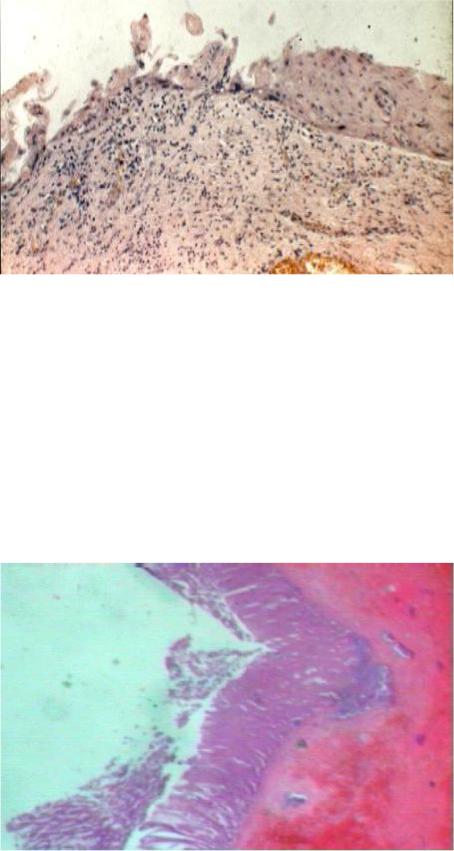

Рис. 85. Макропрепа- рат почки при гема-

тологической форме ОЛБ: малокровие,

набухание коркового вещества почки вследствие зернистой и жировой дистро- фии, сливные крово-

излияния в слизистой оболочке чашечек и лоханки